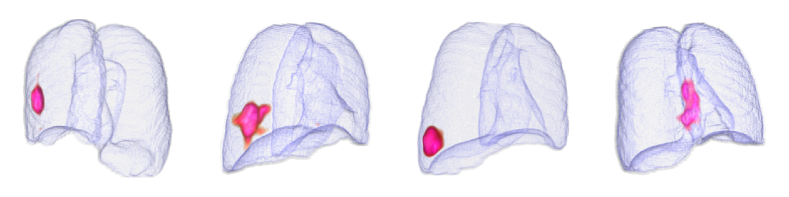

By using the internal clinical dataset from SMC of pneumonia and tuberculosis cases, we experimentally verified the superiority of the proposed VMPR-UAD through various comparative experiments. We also provide quantitative results and 3D abnormal (lesion) localization/visualization results of VMPR-UAD using the internal dataset for pneumonia and tuberculosis in the Supplementary Material to illustrate the superiority of anomaly localization by VMPR-UAD.

Finally, we evaluated the 3D abnormal (lesion) localization performance of the proposed VMPR-UAD. Of the 63 cancer cases in the MSD dataset with ground-truth annotations available, we excluded two cases (cases 38 and 96) of incorrect annotation or showing other diseases. We calculated whether the cancer area predicted by VMPR-UAD (binarized at a certain high-probability threshold) overlapped with the annotated cancer area. As a result, 57 of the 61 cases showed overlapping, demonstrating that VMPR-UAD can localize 3D lung anomalies (cancer in this case) with an accuracy of 93. Some localization examples in 3D data are shown in Fig. L. The red points in Fig. L(b) show the 3D cancer locations that the proposed method estimates with the highest confidence (i.e., location of highest pixel value in the 3D anomaly map). The red points in Fig. L(a) show the ground-truth cancer location. The ground truth and prediction shown in Fig. L confirm that VMPR-UAD correctly finds the lung anomaly 3D region. More detailed visualization results are available in the Supplementary Material. The prediction consistency can also be observed in 2D slices, as shown in Fig. M, where our anomaly localization map indicates correct cancer regions. Hence, the proposed VMPR-UAD can automatically localize or segment lesions without requiring any lesion information (i.e., using only CT slices from healthy subjects) for training.